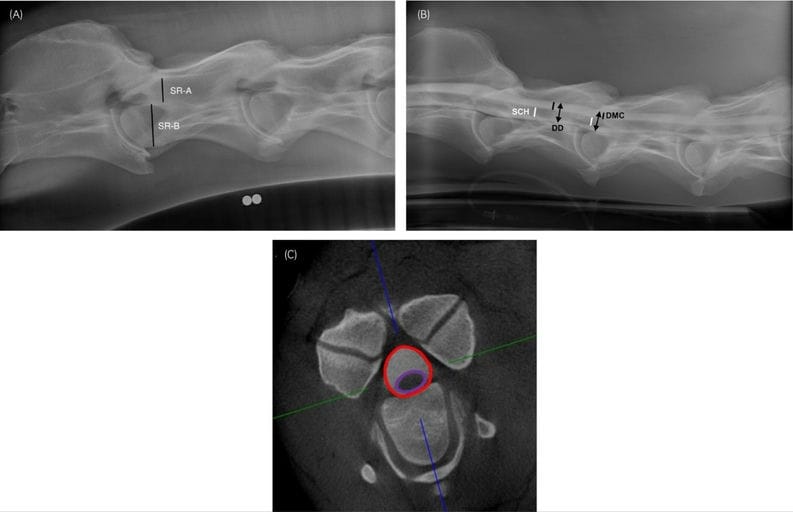

Dimensions obtained from diagnostic imaging. Location of measurements from lateral cervical radiographs (A), radiographic myelograms (B), and CT images (C). In the lateral radiograph the location of C3 is shown (A). In the radiographic myelogram the location of C3 and C3–C4 is shown (B). In the transverse CT image the location of the C4–C5 intervertebral space is shown (C) and the location of the full myelographic area (dural area plus spinal cord area) is identified within the red line and the spinal cord area is identified within the purple line. The blue and green lines are generated by the CT software in multiplanar display. SR-A, intravertebral minimum sagittal diameter; SR-B: maximal height of the cranial vertebral physis; Sagittal ratios are calculated based on SR-A/SR-B. DMC, dorsal myelographic column (black line); DD, dural diameter (double arrowheads); SCH, spinal cord height (white line).